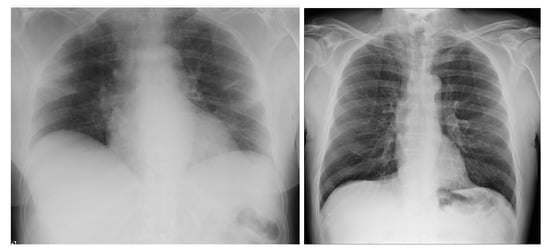

3.4.1. NIH Dataset

3.4.2. COVID-19 Image Data Collection

3.4.3. COVID-19 Radiography

3.4.4. BIMCV COVID19+

3.4.5. Montfort Dataset